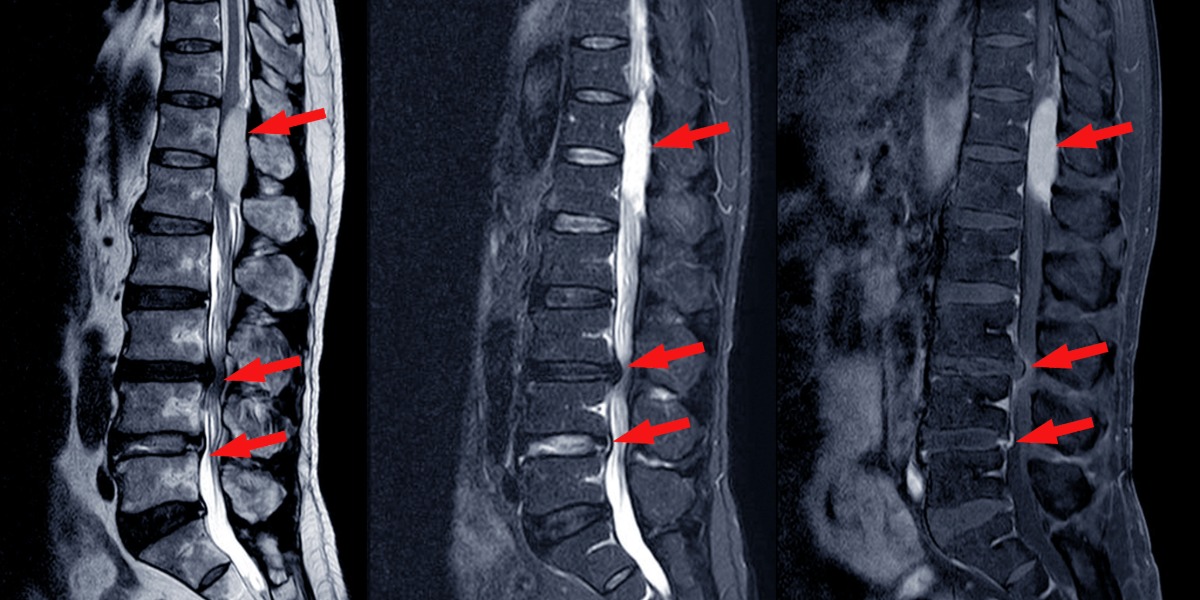

Spinal stenoz tanısı, genellikle hastanın şikayetleri ve fizik muayene bulgularıyla başlar. Ancak kesin tanı için görüntüleme yöntemlerine başvurulur:

- MRI (Manyetik Rezonans Görüntüleme)

- BT (Bilgisayarlı Tomografi)

- Röntgen

Bu yöntemler sayesinde hem daralmanın yeri hem de şiddeti belirlenebilir.